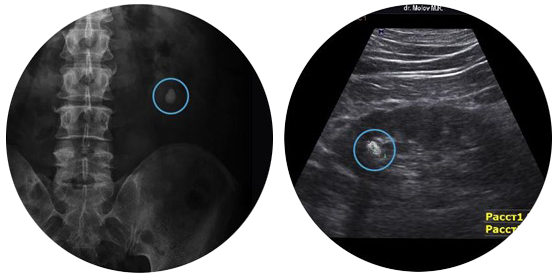

Có hệ thống định vị kép bằng cả tia X và siêu âm để định vị chính xác vị trí sỏi giúp việc tán sỏi dễ dàng và nhanh chóng hơn.

Hình ảnh sỏi ghi nhận bằng tia X (trái) và siêu âm (phải)